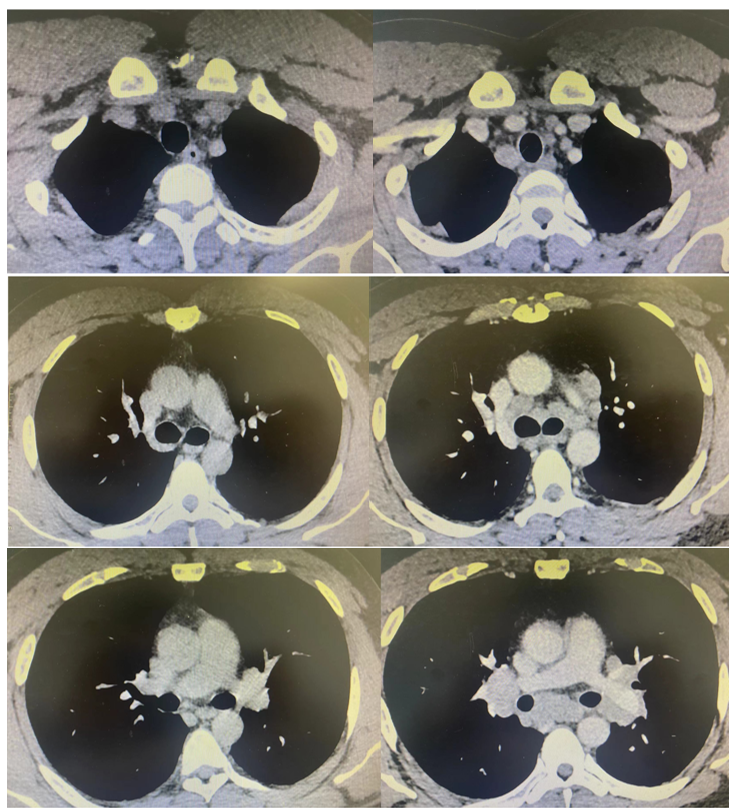

20年哮喘突遇反复发热,「纵膈多发淋巴结肿大」谜何解?